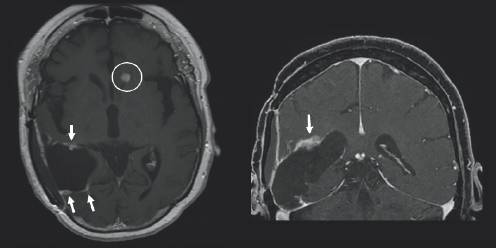

One can also imagine why she would ask herself such a painstaking question, “Why me?”, when she received a (GBM) diagnosis at the age of 66. Janet noted an intense thirst and painful, persistent urination in May of 2017. These symptoms prompted her to visit her primary care physician. Suspicious Janet might have of an overactive bladder or diabetes insipidus, which is characterized by chronic thirst and urination due to an imbalance of fluids within the body, her physician sent her in for imaging. On June 24th, 2017, however, her life would change forever. Janet’s imaging showed a right posterior temporal brain lesion that indicated the existence of a GBM (Fig. 3.1). This location falls on the right side of the head, in the back portion of the brain, synonymous with the location behind the ear. She thought, “I had [cancer] once, I shouldn’t have it again”. She later underwent extensive surgery to resect the tumor. The tumor was analyzed by pathologists at Emory, who shared it was O[6]-methylguanine-DNA methyltransferase (MGMT) methylated, epidermal growth factor receptor (EGFR) viii amplified, and isocitrate dehydrogenase 1 wild type (IDH-1 WT).

Variations of gray color are surrounded by a both a black and light gray boarder. On the left side of the image, there is a white blob outline.

FIGURE 3.1 Brain MRI before surgery. Axial (left) and coronal (right) post-contrast images show a large mass centered in the right posterior temporal lobe with peripheral and irregular enhancement that appears bright after being injected with IV contrast, consistent with glioblastoma.